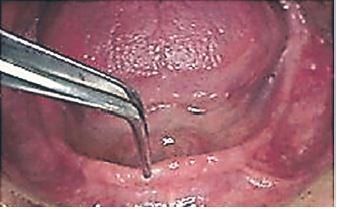

Se pincela la cubeta con adhesivo para prótesis (Coltene, Suiza) y se carga la zona posterior y lingual con silicona de polivinilsiloxano de adición (3M, USA) a través de pistola ; se asienta y estabiliza en boca mediante el mango central (Fig.3 a).Se introduce la punta aplicadora en la ventana y se colma con silicona todo el espaciado sobre el RM (Fig 3 b).Se completa el relleno con silicona por todo el borde vestibular (Fig. 3 c).Durante el tiempo de trabajo del material se combinan movimientos linguales autogenerados y movimientos de labios y mejillas guiados por el operador a fin de registrar la actividad neuromuscular.

Se retira la cubeta de boca, se lava, se critica la impresión (Fig.4), se reposiciona en boca para verificar su retención y estabilidad. Se lava y desinfecta, se encofra y se obtiene el modelo de trabajo en yeso.